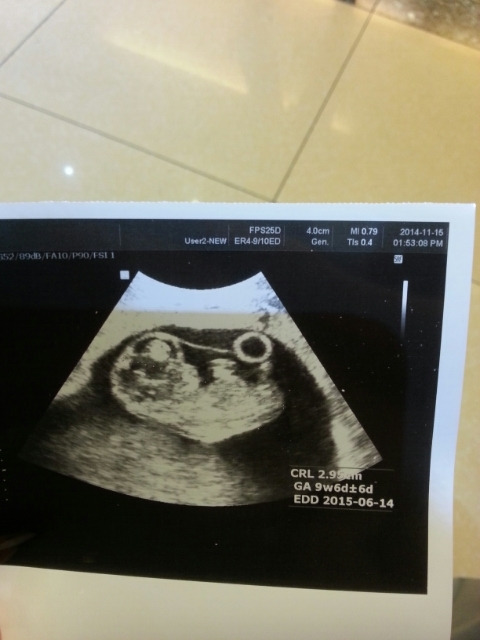

그래서 고마운 마음에 좀 찾아보니 2014년 11월 15일의 귀여운 태교 끄적임이 있어 아껴 올린다.

라미야.

너의 10주 차 사진이야.

2.9cm 라네.

2주 전에 1.4cm 더니. 무럭무럭 커주고 있구나.

엄마랑 은혜산부인과에 가서 이 사진을 찍은 후.

우리 2.9 cm 라미! 만세!! 만만세!!!

14.10.5 최초 초음파 사진

14.11.1 두 번째 초음파 사진